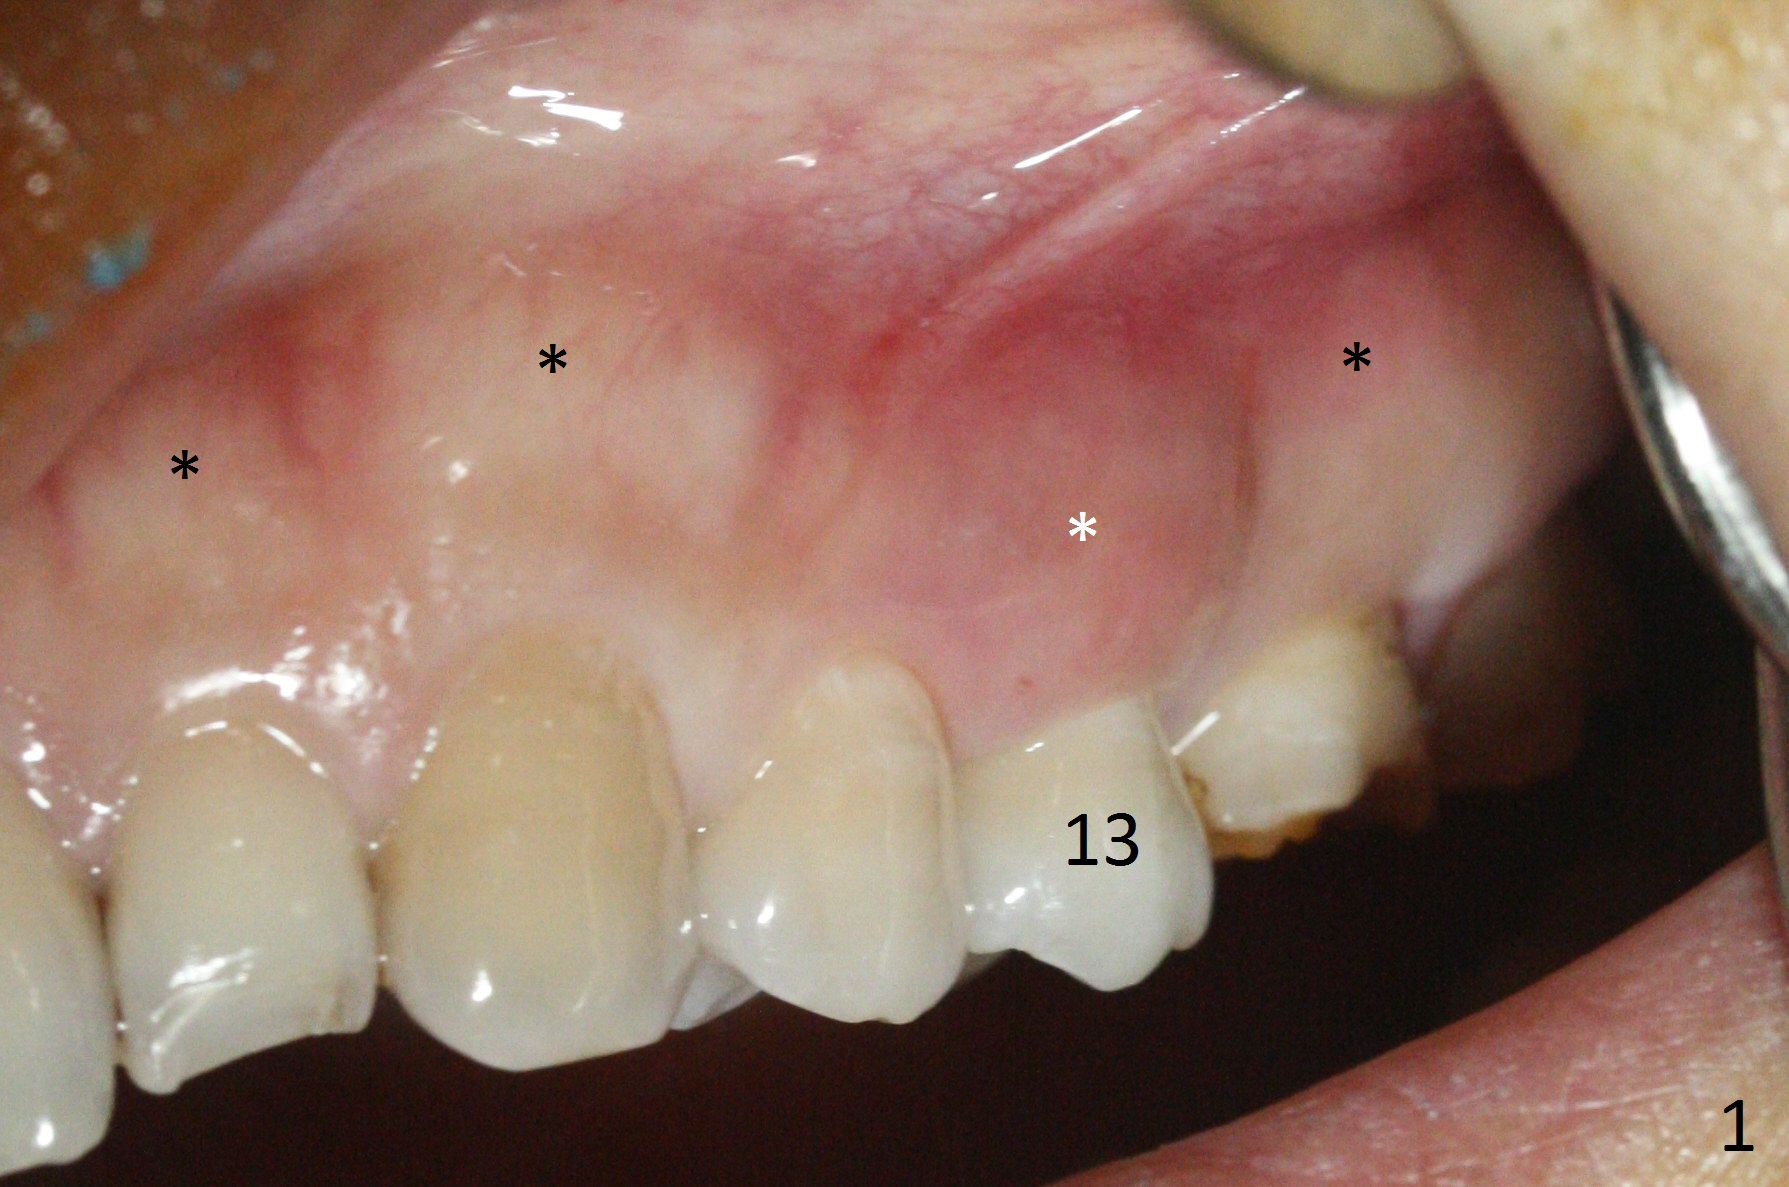

The buccal gingiva over the tooth #13 (Fig.1 white *) with crack (Fig.2 (mesial view of the extracted tooth)) is erythematous with deep buccal (B) pockets, which do not appear to extend the level of exostosis of the neighboring teeth (Fig.1 black *), i.e., coronal to the apical end of the crack with granulation tissue (Fig.2 *). Osteotomy is initiated with a 1.6 mm drill in the palatal aspect of the socket (Fig.3) so that an implant will be placed palatal (Fig.8,11) and there is enough buccal gap for bone graft (Fig.8 *). After withdrawal of 3.3 mm Magic Drill (trephine bur), the osteotomy (Fig.4 O) plug (red outline) is intentionally left in situ. When a 4x11 mm dummy implant is placed (Fig.5 (green outline), 6), the plug is compressed (Fig.5). With placement of a definitive implant (4.5x13 mm, Fig.7 (green), 9), the plug as well as the sinus floor (Fig.4 SF) is lifted (Fig.7 red curved line), 9 (arrowheads)). In brief the autogenous bone is used for sinus lift. There is no intra- or post-op nasal hemorrhage. With a small piece of gauze (Fig.8 G) in the implant well, allograft is placed in the buccal (mainly) and palatal gaps until the level of the implant plateau. Then a 4.5x4(3) mm abutment is placed (Fig.9-10 A). Next another piece of gauze is placed in the space corresponding to the abutment cuff (Fig.11 G) for fabrication of an immediate provisional (Fig.12 P). More bone graft is placed in the soft tissue zone (dual zone technique) after gauze removal and before provisional seating. With dual zone bone graft technique and provisional support, the soft tissue atrophy should be expected to be minimal (Fig.12 *). The zone of exostosis (more coronal) should be much less, since the bone density in the zone is high.

The buccal gingival inflammation subsides 1 week postop (Fig.13,14). There is no bone loss 4 months postop (Fig.15,16). The crown is recemented 6 months post cementation (probably due to short abutment); there is a residual cement (Fig.17 <), which is removed (Fig.18).